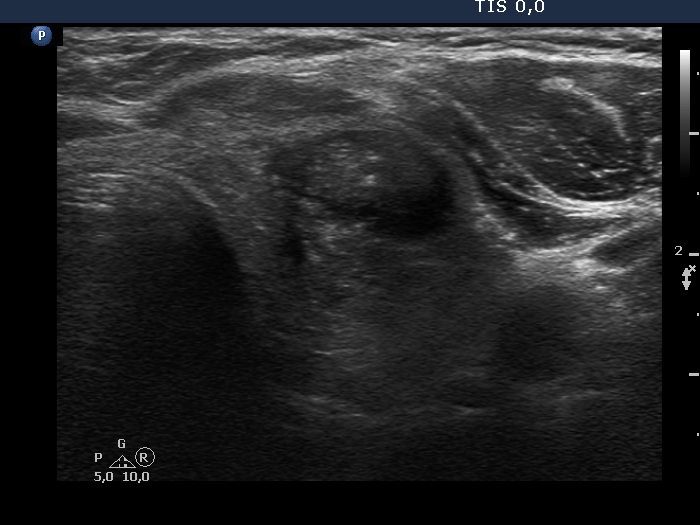

Follow-up investigation 7 years after the first visit (ultrasonographic picture 5)

Left lobe, another transverse scan. The lesion is difficult to project in transverse scan.